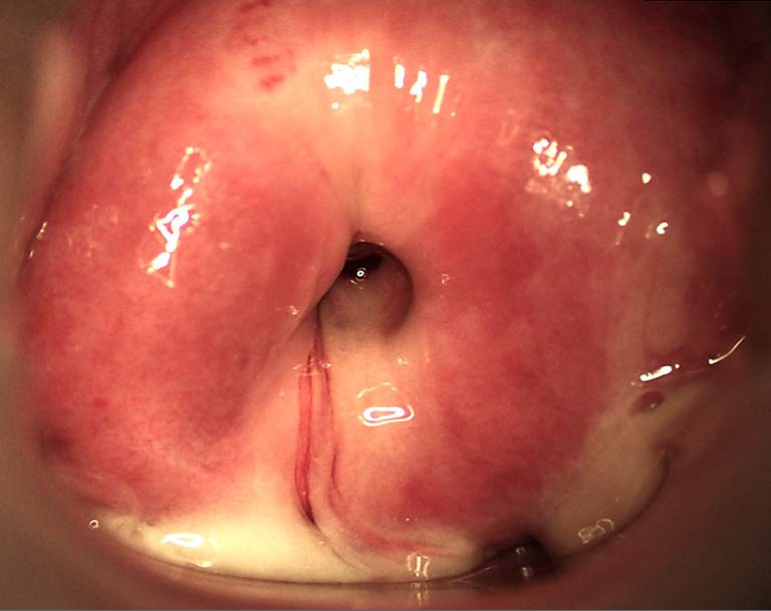

大部分患者无症状。有症状者主要表现为阴道分泌物增多,呈黏液脓性,阴道分泌物刺激可引起外阴瘙痒及灼热感。此外,可出现经间期出血、性交后出血等症状。若合并尿路感染,可出现尿急、尿频、尿痛。妇科检查见子宫颈充血、水肿、黏膜外翻,有黏液脓性分泌物附着甚至从子宫颈管流出,子宫颈管黏膜质脆,容易诱发出血。若为淋病奈瑟菌感染,因尿道旁腺、前庭大腺受累,可见尿道口、阴道口黏膜充血、水肿以及多量脓性分泌物。

急性子宫颈炎黏液脓性分泌物

1.两个特征性体征,具备一个或两个同时具备:

(1)于子宫颈管或子宫颈管棉拭子标本上,肉眼见到脓性或黏液脓性分泌物。

(2)用棉拭子擦拭子宫颈管时,容易诱发子宫颈管内出血。